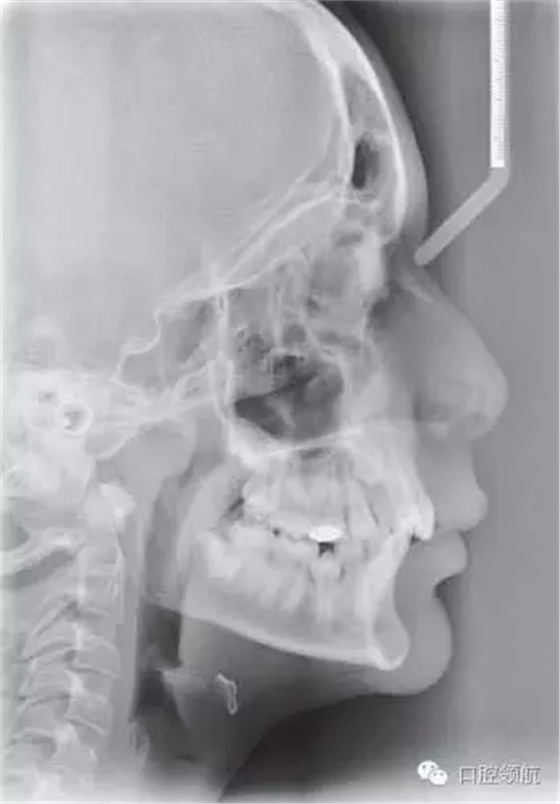

圖2.43顯示的是該患者的頭側位片,請總結其錯牙合情況

● 13歲男性患者,I類關系,輕度骨性II類,均面型。

● 雙側磨牙I類關系,中線齊,雙側尖牙1/2牙尖II類關系。

● 另外伴有:

○ 1. 異位UR3。

○ 下頜第二前磨牙阻生。

○ 深覆牙合。

○ 上下牙列均存在擁擠。

● 骨性因素:輕度骨性II類畸形,下頜后縮,并導致尖牙1/2牙尖的II類關系。

評價軟組織側貌及其和治療方案的關系

軟組織側貌豐滿。鼻唇角在90°~110°之間,上唇略靠前,唇紅飽滿。上下唇厚且健康。頦唇溝相對較深??偟膩碚f,軟組織側貌是可以接受的,并且在拔牙內收后仍不失美觀。